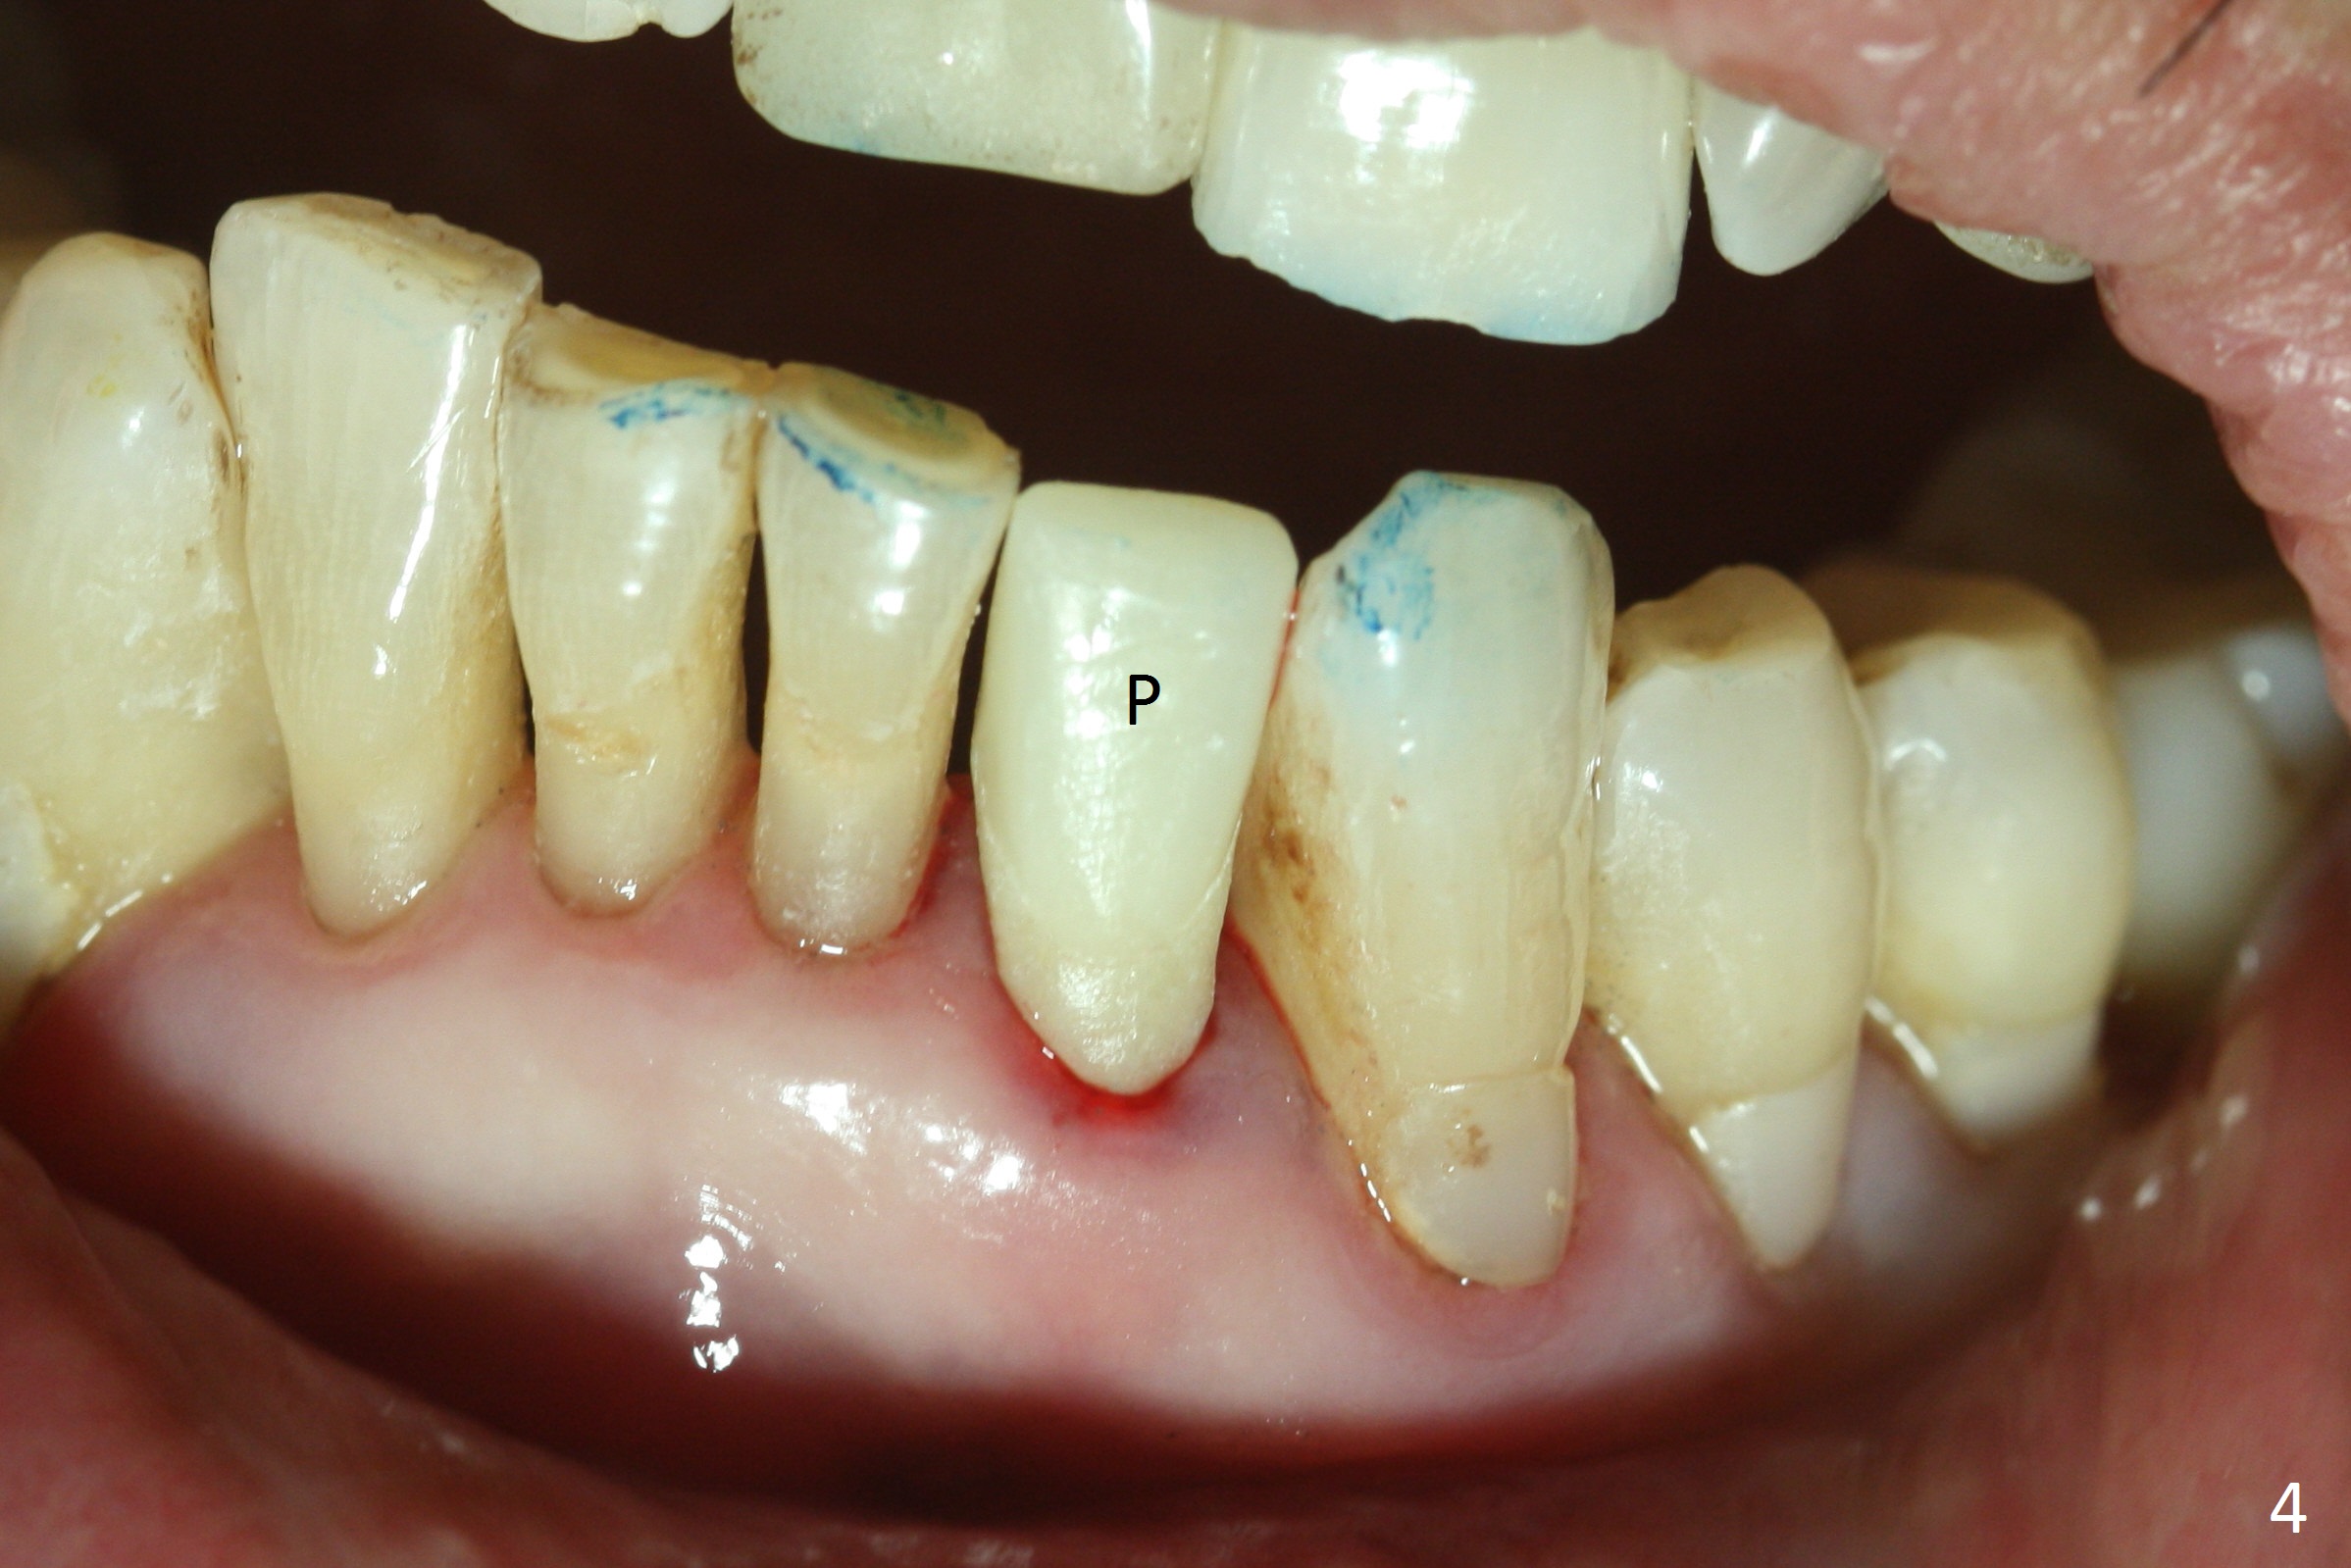

The tooth #23 is going to be extracted because the patient cannot masticate normally with mobility (Fit.1). The gingival depth is measured 2-4 mm after extraction. The 1st intraop PA taken with 1.2 mm drill for 16 mm shows the mesiodistal width is 5.11 mm (Fig.2); a 2.5x14(2) mm 1-piece implant is placed with >35 Ncm (Fig.3 with allograft placed). Following abutment preparation, an immediate provisional is fabricated to close the socket (Fig.4 P). There is no bone loss (Fig.5) or gingival inflammation (Fig.6 after reprep) 3 months postop. The narrow implant (2.5 or 2.0 mm) is indicated in the narrow edentulous space. The distal crest seems to be reduced in density and lower in height 1 year 7 months (Fig.7) and 1 year 11 months (Fig.8) post cementation. The severity does not worsen probably related to use of water pik. The crown looks bulky probably due to too large the abutment and too buccal placement of the implant (Fig.9, 10, as compared to Fig.1). A 2 mm implant may help?